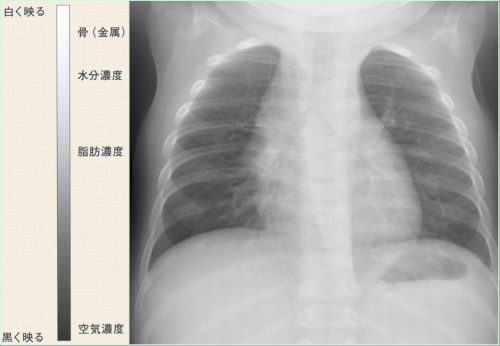

呼吸器疾患診療における胸部HRCT画像読影のポイント(静止画)|べーリンガープラス, X線診断の基礎知識|胸部写真の読み方|太田東こども&おとな診療所|こどもとおとなの病気について、気軽に相談できる診療所です。,

X線診断の基礎知識|胸部写真の読み方|太田東こども&おとな診療所|こどもとおとなの病気について、気軽に相談できる診療所です。, レジデントノート増刊:読影力がグッと上がる!胸部X線写真・CTの読み方、考え方〜疾患別に読影の基本と各科での経過観察のポイント、撮影のタイミングがイチからわかる! - 羊土社,